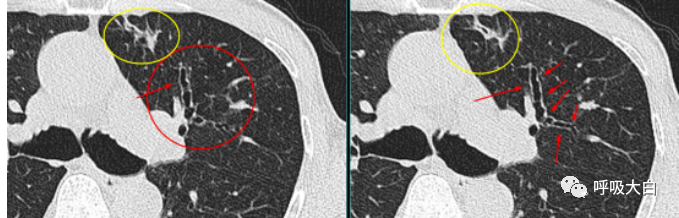

反晕征是一种特殊的胸部 CT征象,表现为环状高密度影围绕着中央密度较低的肺部阴影。起初认为,反晕征为隐源性机化性肺炎的特征性的征象;但此后被报道见于多种其他疾病,如肺副球孢子菌病、肺淋巴瘤样肉芽肿病、肺结节病、侵袭性肺真菌病、活动性肺结核及肉芽肿性多血管炎( 原韦格纳肉芽肿),亦可见于继发于感染或胶原血管病的机化性肺炎。

在肉芽肿性疾病,其外围的环状高密度影不光滑, 而在非肉芽肿性疾病,外围的高密度影则较为光滑,此特征可用于初步判断病理性质。

隐源性机化性肺炎(COP):

结节病:

肉芽肿性多血管炎(GPA):

肺栓塞: